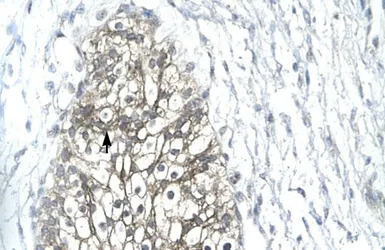

IHC-P analysis of human urinary bladder tissue using GTX77841 MMP19 antibody at 4.0-8.0μg/ml.

IHC-P analysis of human colorectal cancer tissue and human small intestine tissue using GTX77841 MMP19 antibody at 1:100. Antigen retrieval using citrate pH 6.0 solution at 96 degree C for 15 minutes in a pressure cooker.